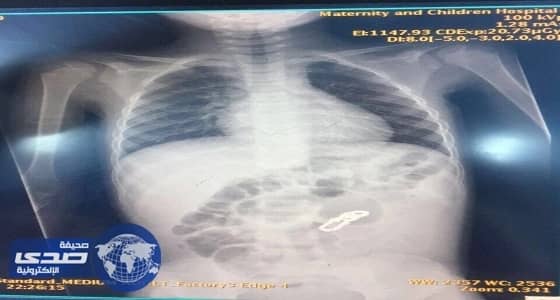

وأتضح من خلال الأشعة التي أجريت له في أحد المستشفيات الخاصة سابقاً وجود جسم غريب يشبه القطع المعدنية الشبكية في البطن.